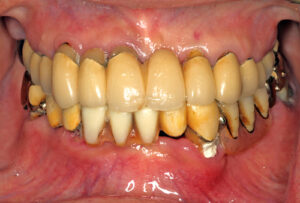

上下顎オールオン6症例

BEFORE AFTER 63歳男性/上顎6本・下顎6本 【治療内容】 全体的に歯が揺れてお食事がとりづらくなり、来院さ…